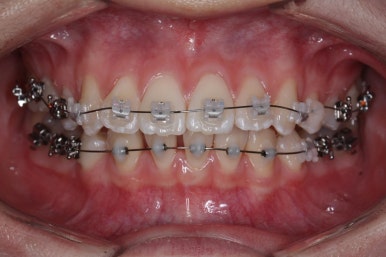

부산교정 키다리아저씨치과에 처음 내원하셨을 때의 입안 모습입니다.

윗니가 삐뚤어져 있고, 아래앞니 사이에는 틈이 듬성듬성 보입니다.

아랫니를 살펴보면 화살표 표시를 해둔 송곳니~송곳니 사이에 치아가 1개 모자랍니다. 원래는 4개의 앞니가 있어야 하는데, 3개 밖에 없었습니다. 이런 결손치아의 경우는 다음과 같은 문제가 생깁니다.

부산교정 키다리아저씨치과에서 장치를 부착하고 교정치료를 시작하였습니다.

이번에 부착한 장치는 엠파워클리어라고 하는 자가결찰 세라믹 장치입니다. 흔히들 클리피씨 장치로 많이 알고 계신 장치가 바로 자가결찰 세라믹 장치인데요.

자가결찰 세라믹 장치 중 또 다른 하나가 엠파워 클리어입니다. 클리피씨는 일본제품, 엠파워 클리어는 미국제품으로 제조회사가 다를 뿐 큰 분류에서는 비슷한 장치라고 보시면 되겠습니다.